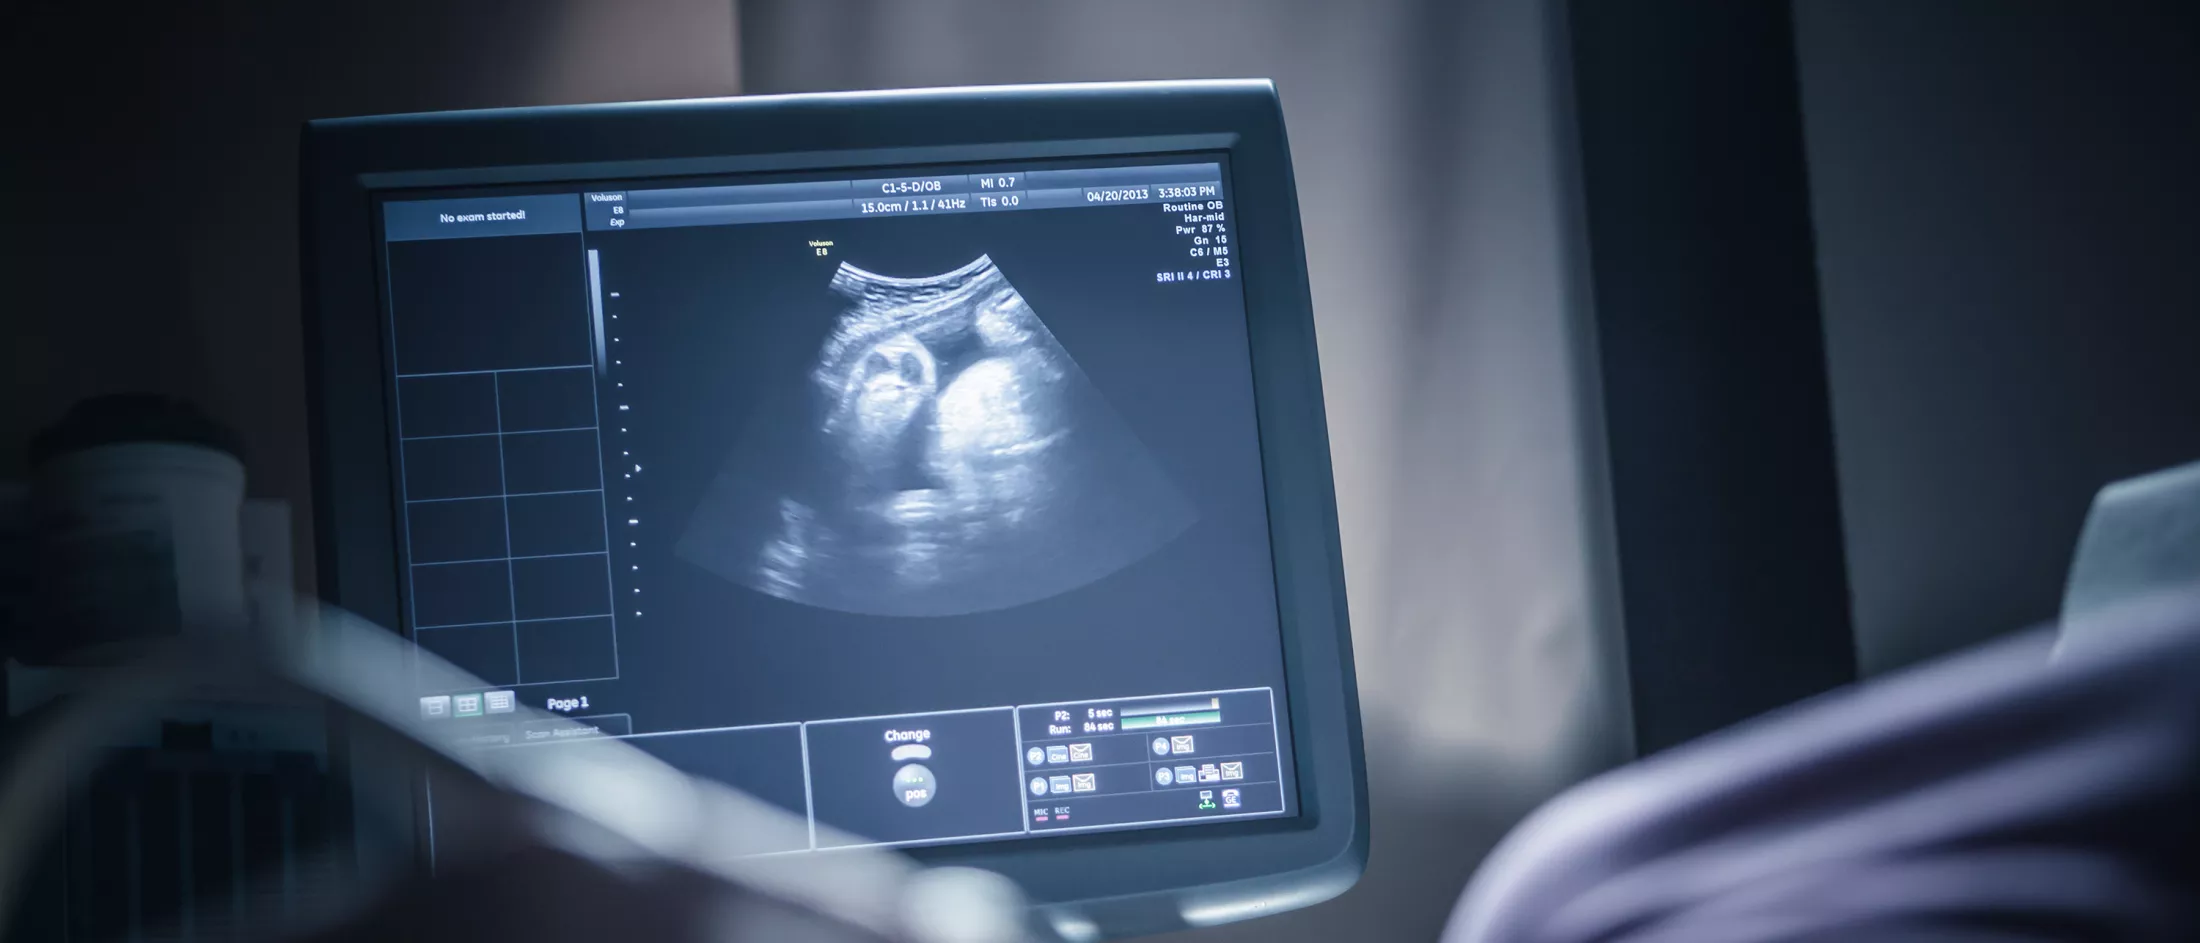

Pregnant woman receiving a sonogram